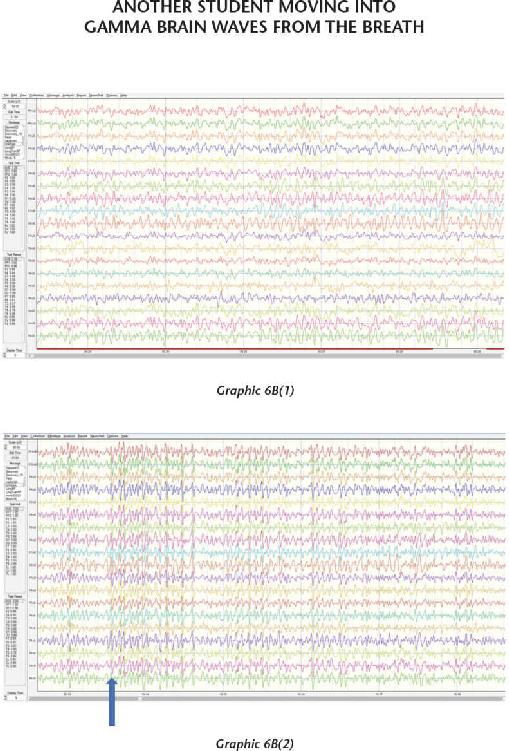

We have thousands and thousands of brain scans that prove those changes were not just imagined in their minds but actually took place in their brains. Several of the students we measured accomplished those changes within four days (the length of our advanced workshops). The scientific teams I’ve assembled have taken brain scan recordings using quantitative electroencephalogram (EEG) measurements before and after workshops as well as real-time measurements during the meditations and practices themselves. I was not only impressed with the changes, but shocked by them—they were that dramatic.

At the end of 2013, something mysterious started occurring. We started seeing brain scan recordings that puzzled the researchers and neuroscientists who came to our events to study my work. The high amount of energy in the brain that we were recording while a student was in certain meditations had never been recorded up until this point. And yet we were seeing these off-the-charts readings again and again.

When we interviewed the participants, they reported that their subjective experience during the meditation was very real and mystical, and that this either profoundly changed their view of the world or dramatically improved their health. I knew in those moments that these participants were having transcendental experiences in their inner world of meditation that were more real than anything they had ever experienced in their outer world. And we were capturing those subjective experiences objectively.

That has become a new normal for us now, and as a matter of fact, we can often predict when these high amplitudes of energy in the brain will occur, based on certain indicators and signs that we have seen for years now. In these pages, I want to demystify what it is to have an interdimensional experience as well as provide the science, biology, and chemistry of the organs, systems, and neurotransmitters that make this happen. It is my hope that this information will give you a road map for how to create such experiences for yourself.